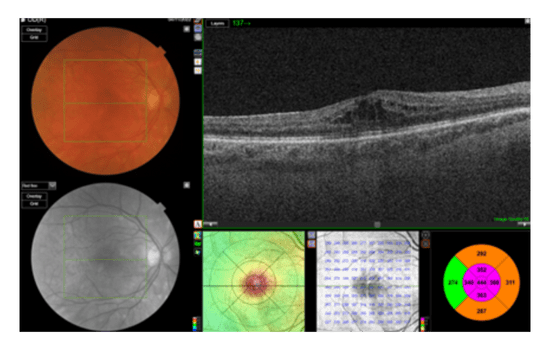

A 62-year-old patient sought a second opinion following a diagnosis of intraocular inflammation in both eyes, which was more severe in the right (BCVA: 0.4 LogMAR) than the left (BCVA: 0.3 LogMAR). An optician diagnosed vitritis. A month later, a local hospital diagnosed the patient with birdshot chorioretinopathy and initiated treatment that included Ozurdex intravitreal therapy in both eyes, oral prednisolone, and methotrexate.

Fundus Color (OD)

OCT (OD)

Fluorescein Angiography (OD)